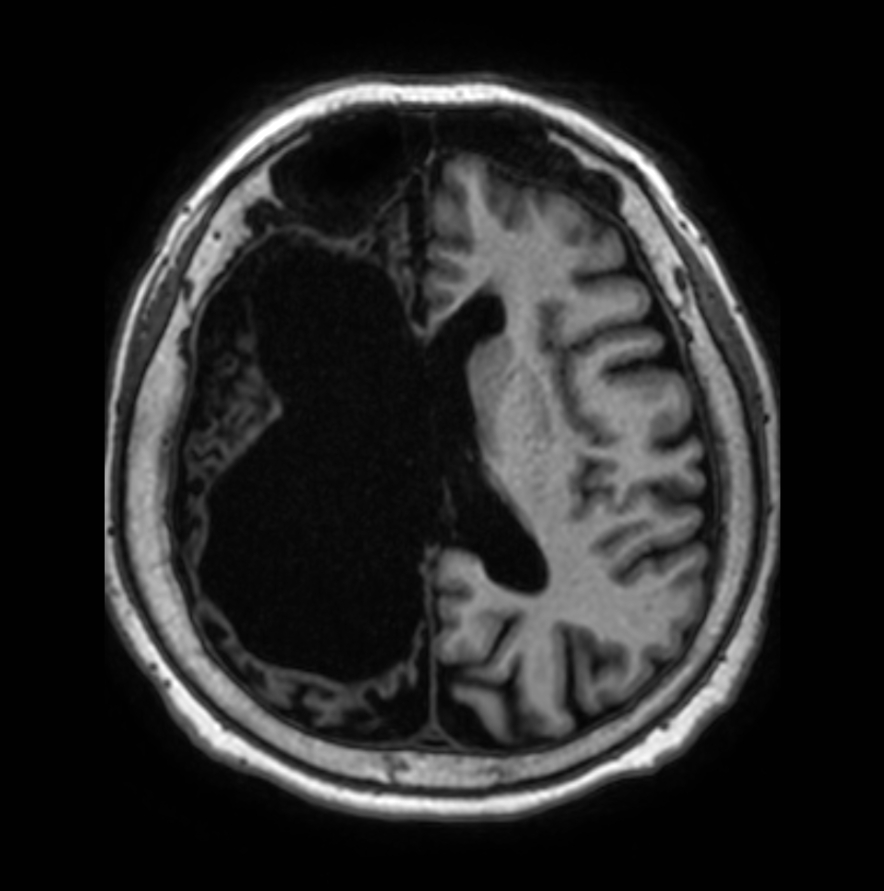

Axial T1w 3D TFE

Coronal T1w 3D TFE